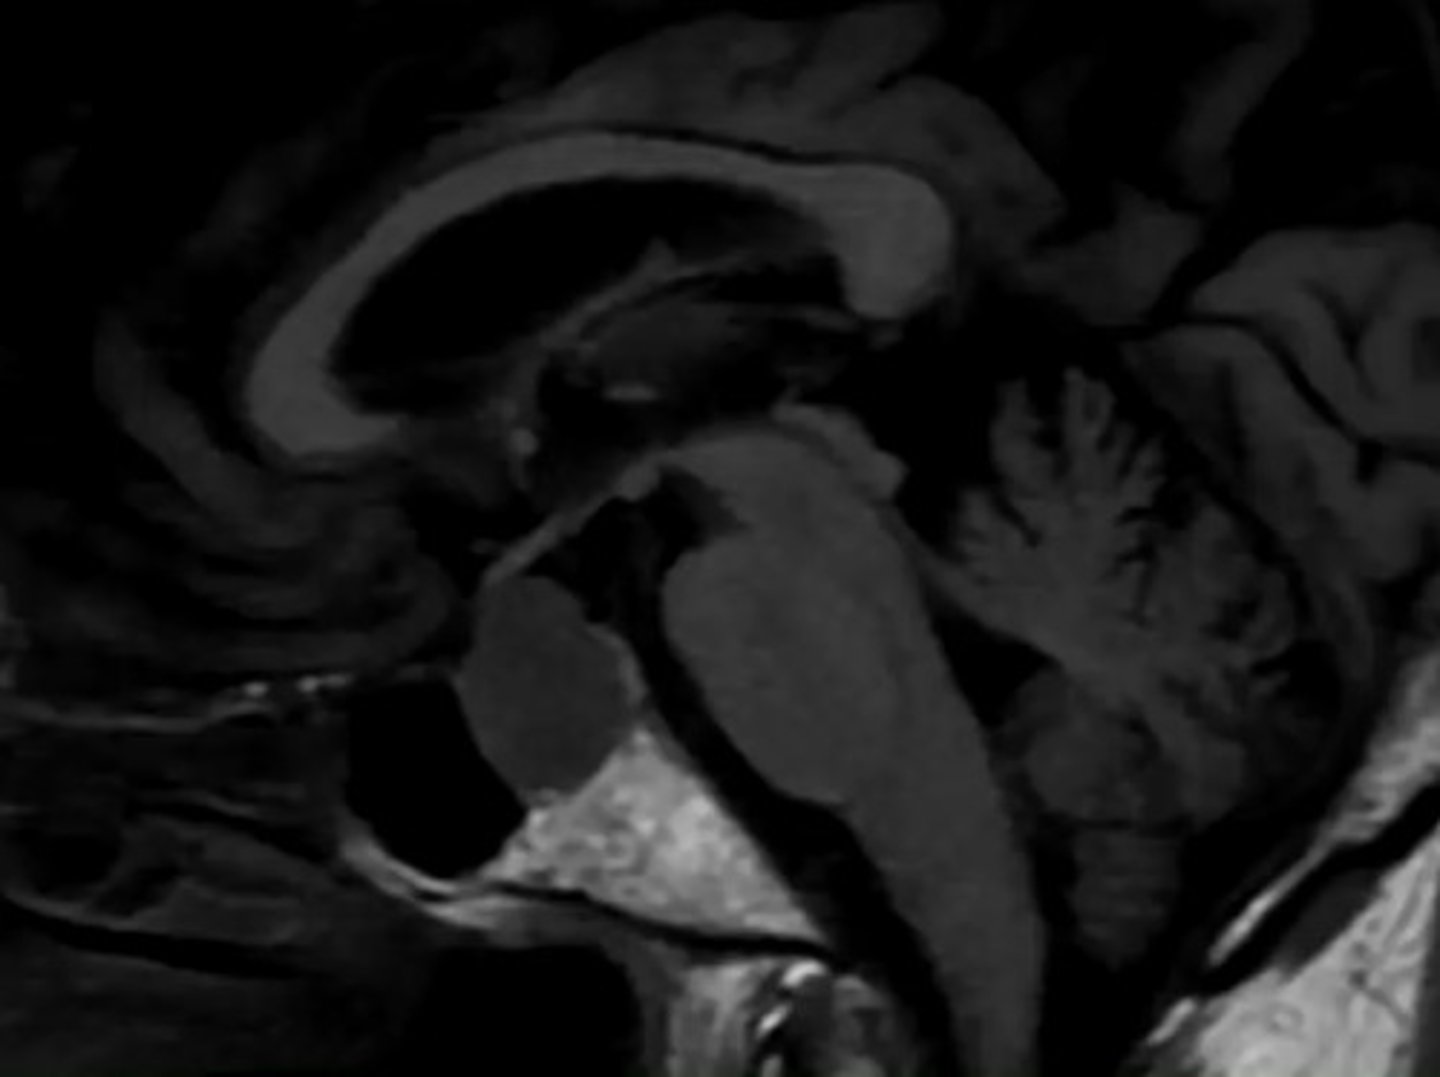

What is something to consider with MRI or CT when imaging for the pituitary?

You might have to order special testing, to get thin enough slices to catch smaller tumors